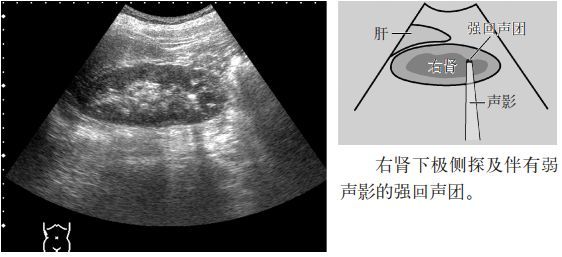

临床必备肾结石输尿管结石超声表现一览